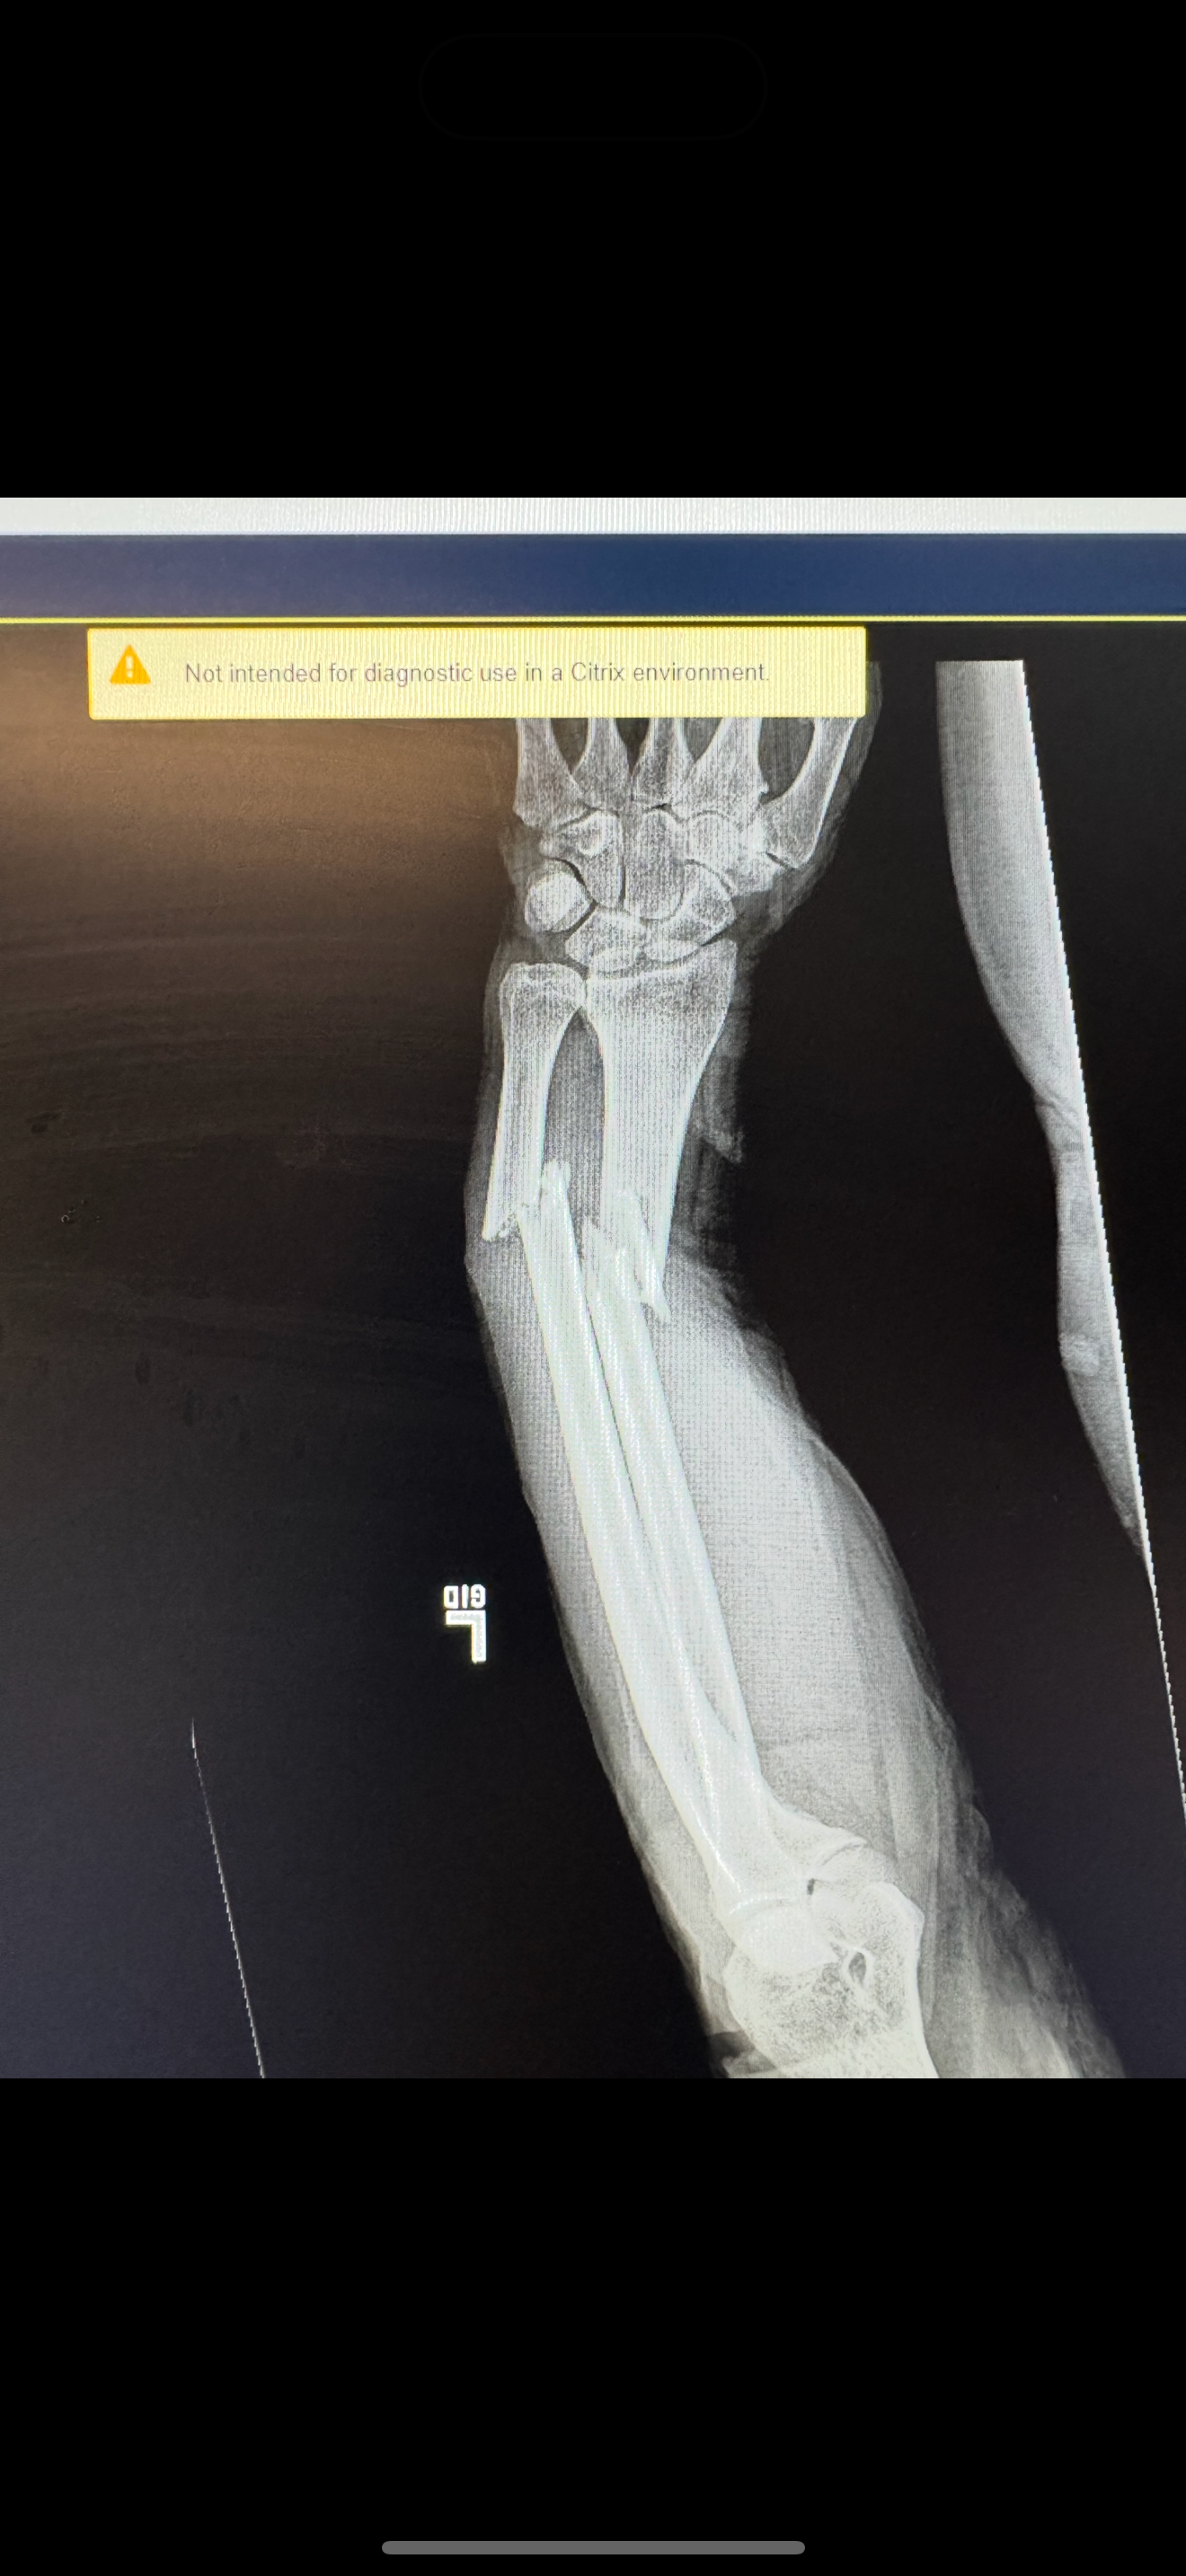

Our family is facing an unimaginable situation. Many of you know my parents and their love for travel. They recently departed Colorado, excited to embark on an adventure landing them in Missouri to spend Christmas with our Grandpa. Late Saturday afternoon in New Mexico, our parents and their dog Pebbles were violently struck by a drunk driver. The impact was so severe that our father suffered multiple broken bones and had to be airlifted to a trauma center for emergency surgery. Our mother was taken by ambulance to a different hospital for urgent treatment and extensive testing.

Both of them are currently stable, but the road ahead is long. While Darlene has been recently released, she will be bedridden for several more days at a local hotel. Glenn will continue to be in the ICU until he improves and will likely be moved to a rehab facility. Being out of town and facing this traumatic situation is definitely an added layer of complexity for all. Our parents are facing:

• Major surgeries and ongoing medical care